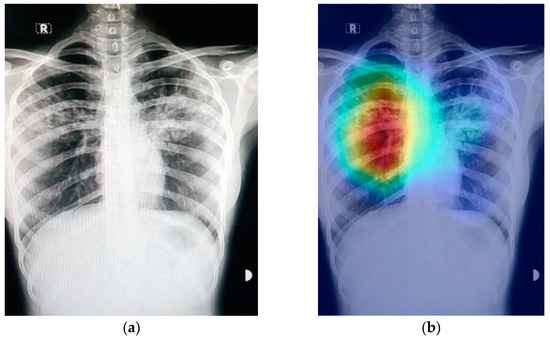

The prediction result for a chest X-ray of a local COVID-19-positive patient for each model is given in Figure 13a–d. The DenseNet-121 had the highest probability percentage of COVID-19, i.e., 99.9%. In order to highlight the area where the model is paying the most attention during feature extraction, the Grad-CAM technique was applied. The Grad-CAM results of all four models under study are given in Figure 14. Moreover, the results of the predicted normal patients for each model are shown in Figure 15a–d. Considering these results, the MobileNet has the highest probability of 96.8% for the prediction of a normal chest X-ray.

Figure 14.

Grad-CAM results on local Pakistani COVID-19 chest X-ray: (a) DenseNet-121; (b) VGG16; (c) MobileNet; (d) ResNet-50.